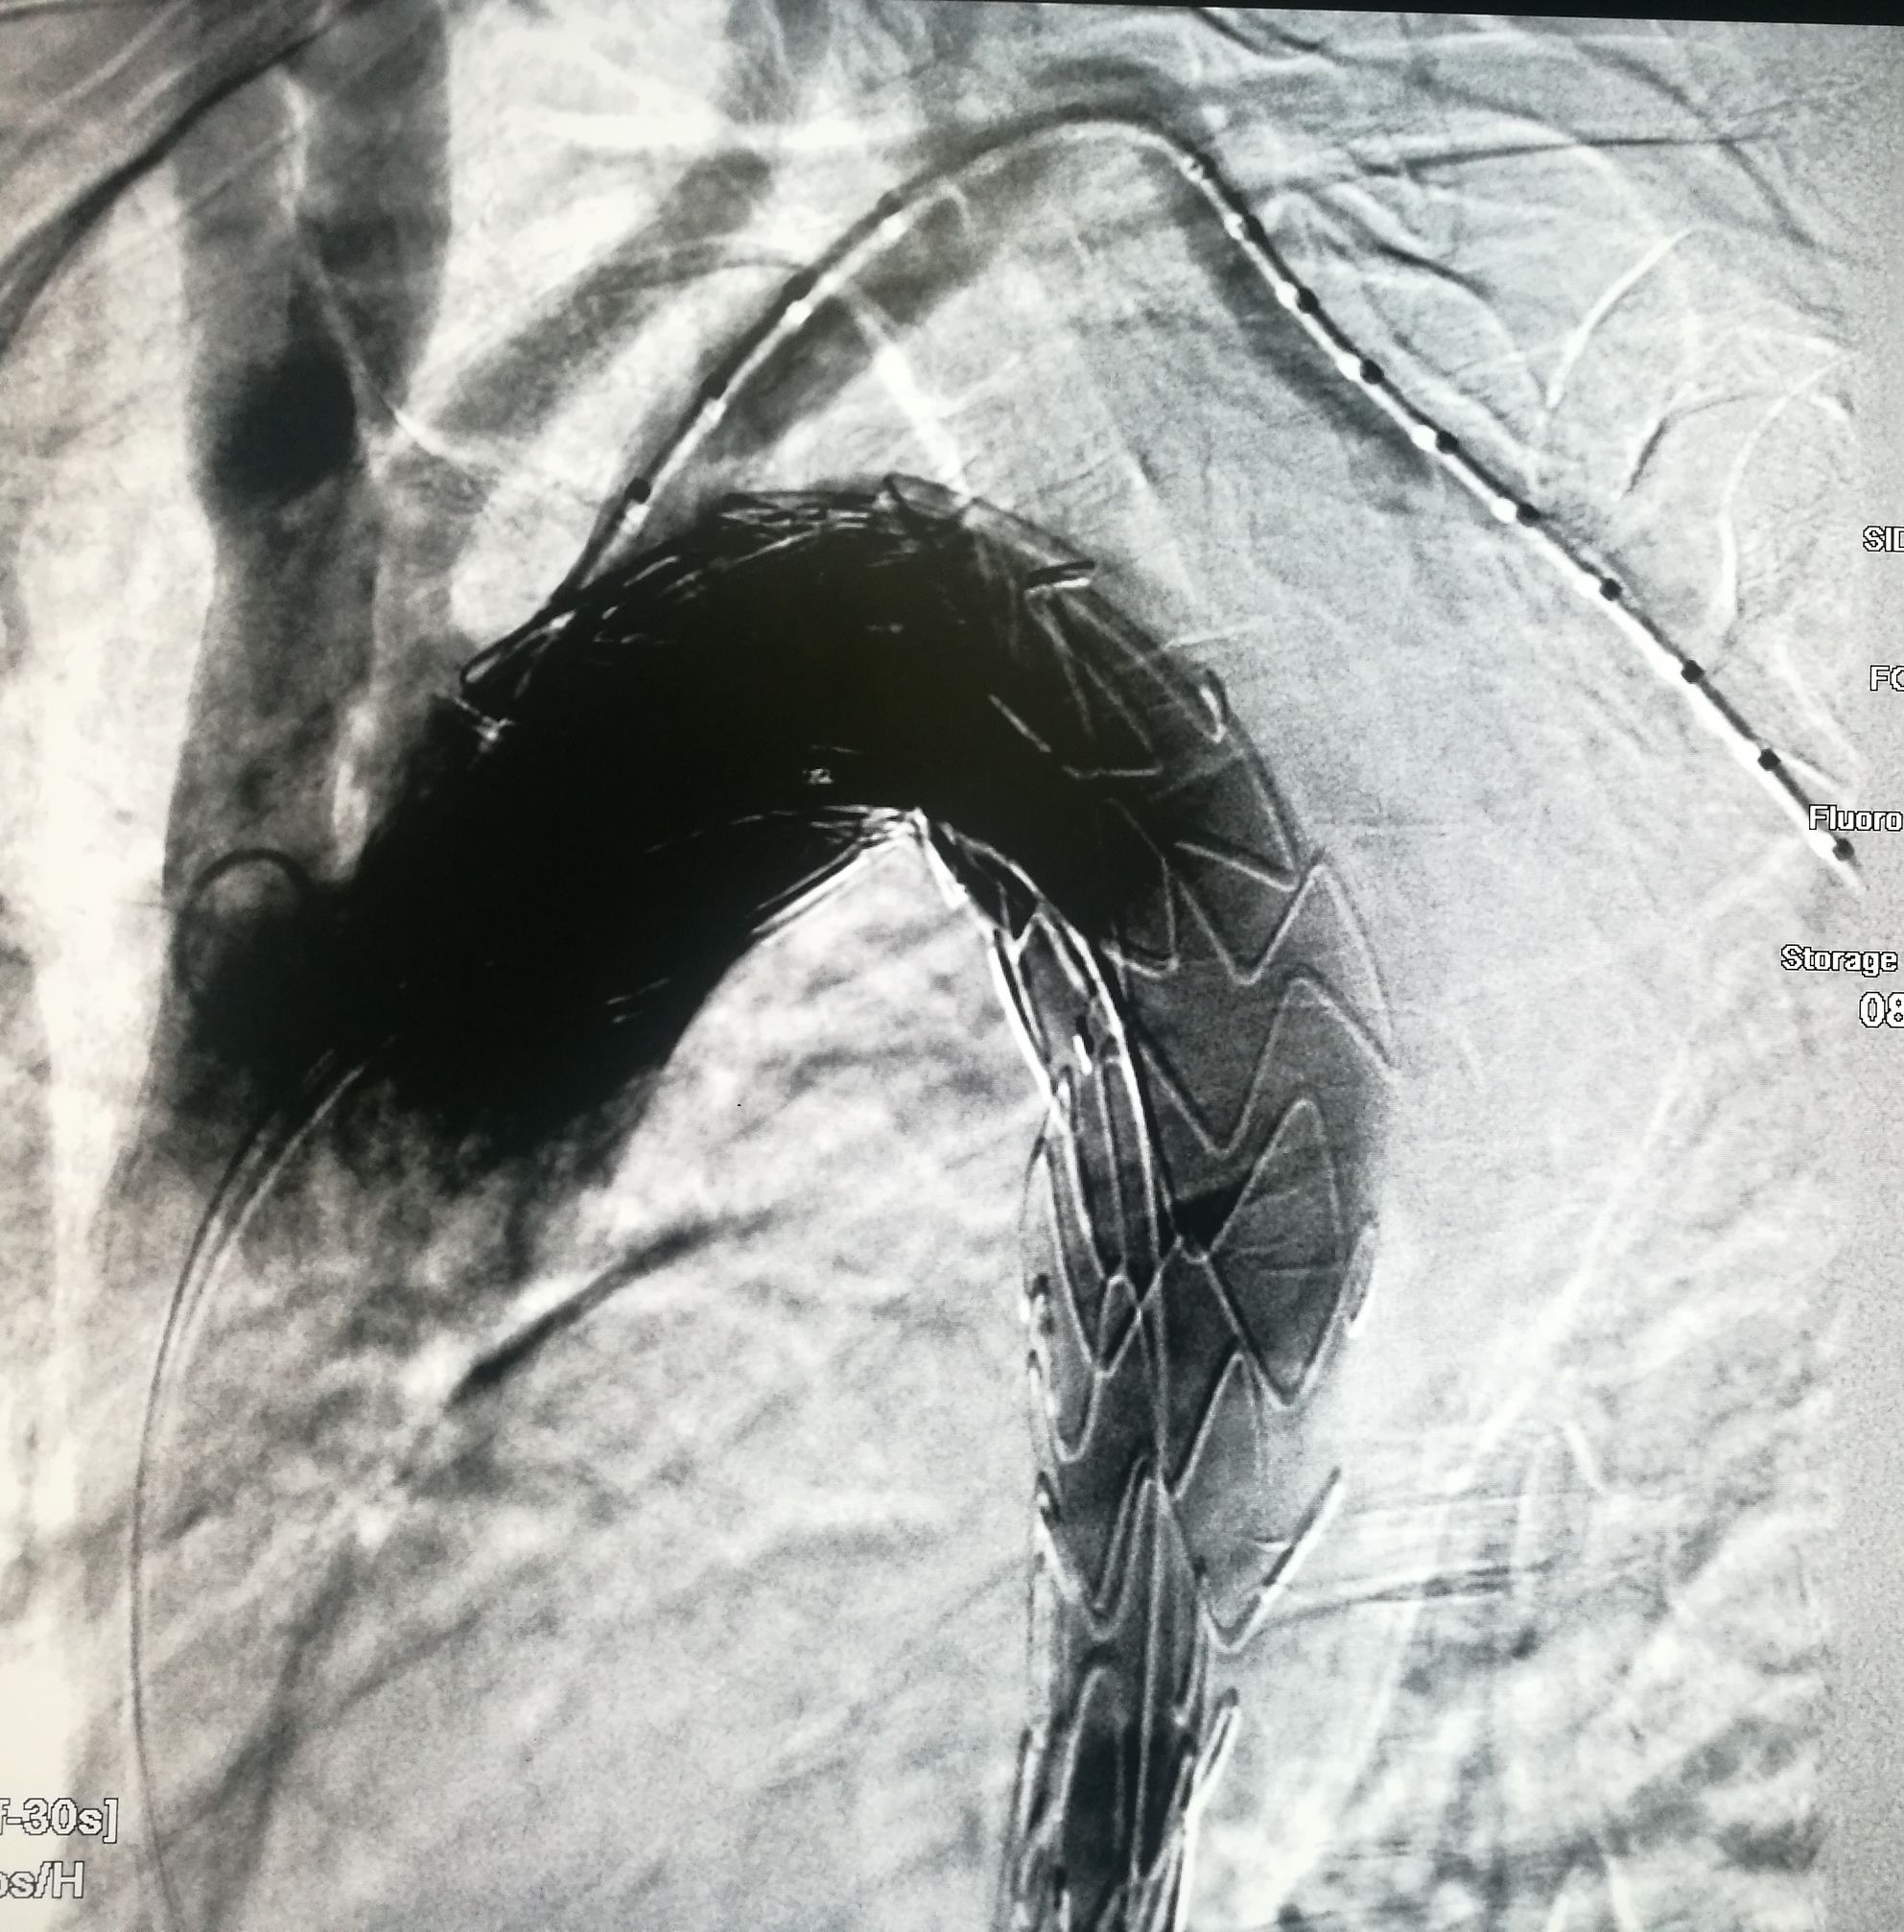

手术在局麻下进行,经右股动脉穿刺置管到升主,经左桡动脉穿刺植入金标猪尾导管,造影,为确认真假腔,加做右前斜位造影,确认股动脉导管在真腔内,测量后植入覆膜支架。由于扭曲严重(腹主,膈肌附近,弓降),支架最初并未贴服大湾侧,支架送过锁骨下动脉后适当回撤,请拉释放导丝,此时支架整体向大弯侧轻微移动,考虑应力已经得到缓解。完全释放支架,定位良好,封堵完全无内漏。

尽管有加硬导丝,但从二维影像上看,支架并未贴着大弯侧走行

慢性夹层能封堵如此完美的少,假腔压迫导致吞咽困难的也不多,慢性夹层血管扭曲严重,手术难度较大。血管病争取早发现早治疗效果好。